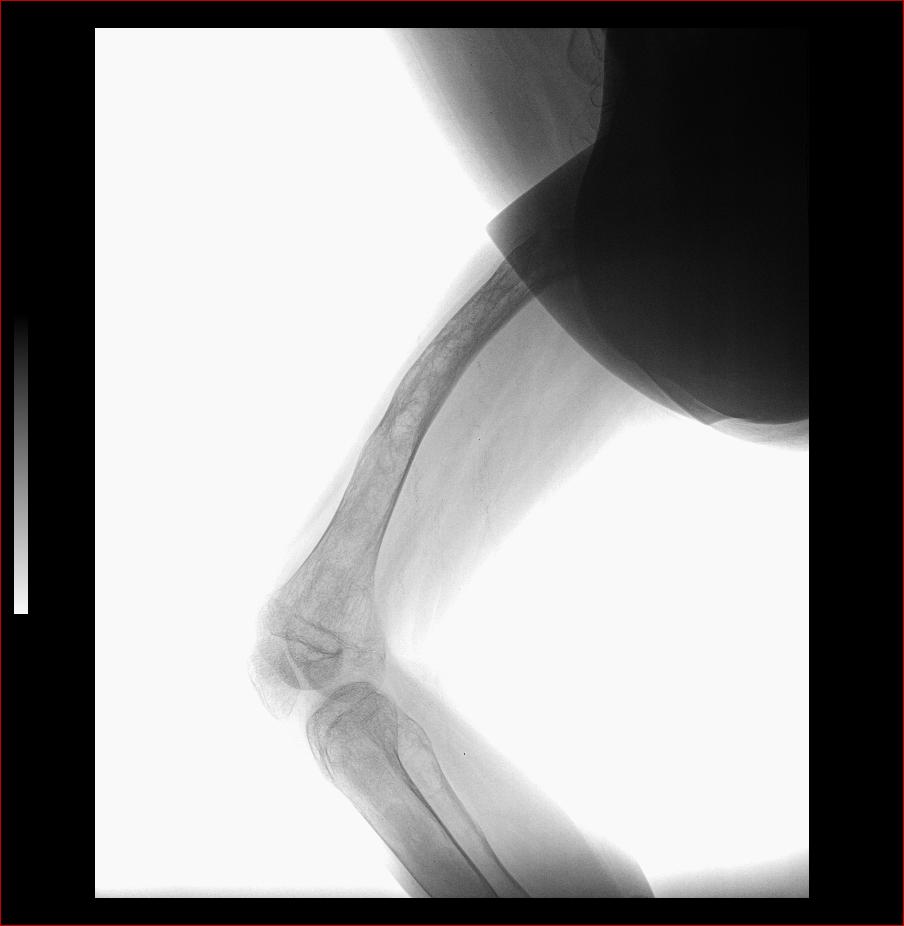

标题: X3602:F17Y,右腿畸形 [打印本页]

标题: X3602:F17Y,右腿畸形

股骨藏刀样畸形改变,骨髓腔消失,骨皮质结构紊乱,典型的骨纤维异常增殖症。

股骨骨纤维异常增殖症并畸形、病理性骨折。

股骨骨纤维异常增殖症并病理性骨折。

考虑股骨骨纤维异常增殖症并病理性骨折。